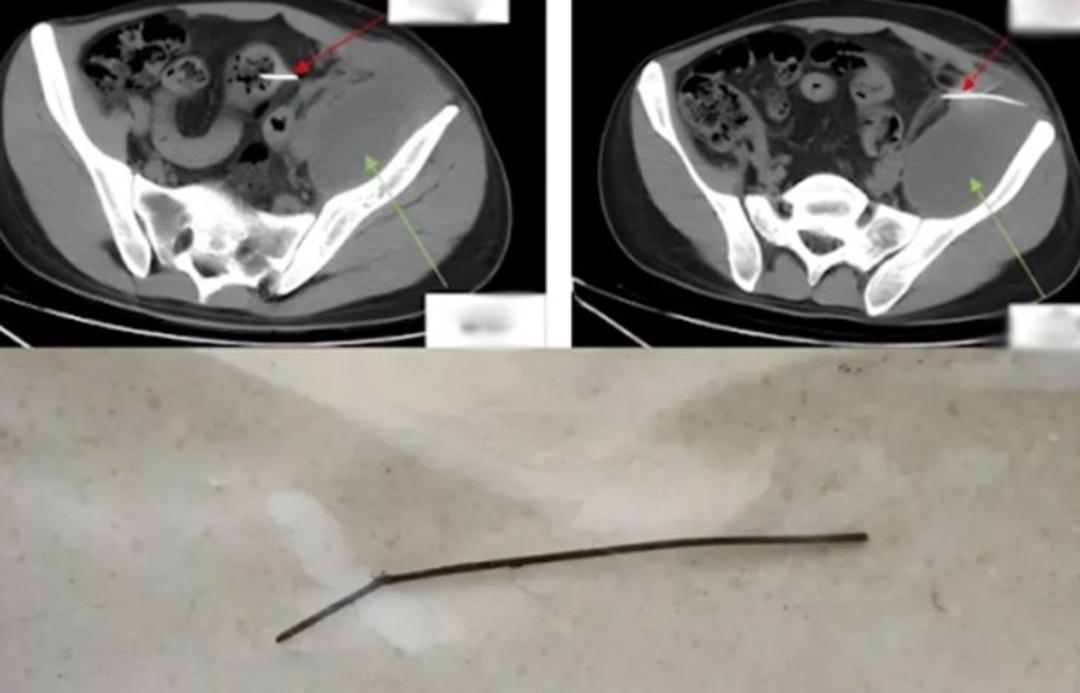

Hastanede röntgen çekildikten sonra sol karın boşluğunun bağırsak duvarında sivri uçlu yabancı bir cisim tespit edildi. Bu cismin iltihaplanmaya ve bağırsak delinmesine neden olduğu ortaya çıktı. Uzun süredir devam eden enfeksiyon 180 mililitre irin üretmişti, bu yüzden doktorlar 2 saat 40 dakika süren laparoskopik bir ameliyat gerçekleştirdiler ve yabancı cismi çıkartmayı başardılar.

Yabancı cismin 13 cm uzunluğunda çöp şiş olduğu tespit edilirken 28 yaşındaki hasta ameliyattan iki gün sonra yeniden yürüyebildi. 5 gün sonra hastanede daha rahat hareket edebildi. 16 gün sonra hastaneden taburcu edildi.